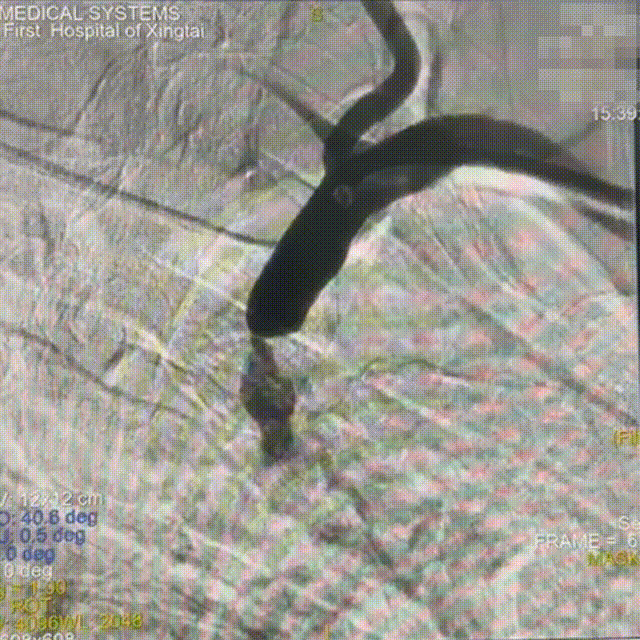

术后即刻造影

狭窄解除,前向血流好转。

狭窄解除,盗血消失。